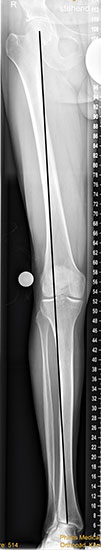

Die Standardröntgendiagnostik bei Fußfehlstellungen und asymmetrischen Arthrosen besteht in stehenden Aufnahmen des Fußes in 2 Ebenen (dorsoplantar und lateral), sowie einer stehenden ap Aufnahme des Sprunggelenks und eine „hindfoot alignment view“ nach Saltzman, mit der die inframalleoläre Rückfußachse beurteilt werden kann 7. Ganzbeinstandaufnahmen sind essentiell, um die mechanische Achse der gesamten unteren Extremität zu analysieren. Zur genauen Analyse des Knorpelzustands bietet sich die Kernspintomographie an. Für spezielle Indikationen steht das SPECT-CT zur Verfügung.

Grundsätzlich muss bei Korrekturen im Bereich der distalen Tibia immer die mechanische Achse der gesamten unteren Extremität einschließlich der Rückfußachse mit einbezogen werden. Korrekturen werden idealerweise von proximal nach distal durchgeführt, da eine Änderung des proximalen Alignements sich immer auch distal auswirkt 16183.